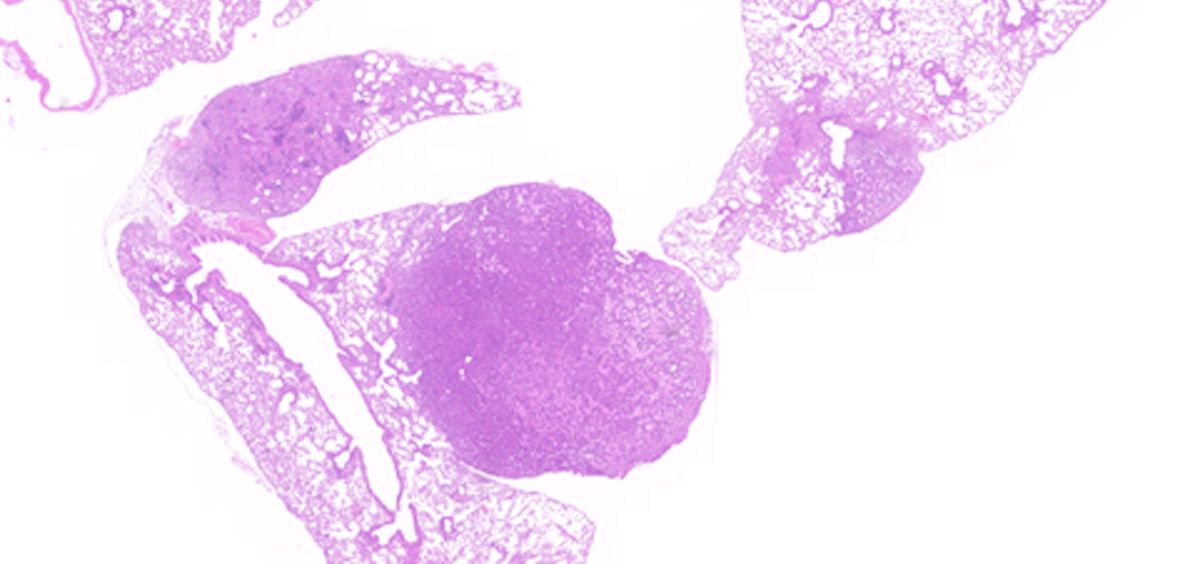

El estudio fue realizado a partir del diseño de dos modelos de ratón genéticamente modificados que carecen de KRAS4B, y expresan únicamente la proteína KRAS4A, bien en su forma sana o con la mutación G12V (KRAS4AG12V), y se centró principalemnte en el tumor de pulmón y el desarrollo embrionario.

La proteína KRAS4AG12V por sí sola, en ausencia de KRAS4B, es capaz de promover la formación de tumores en el pulmón e inducir metástasis en el 20% de los casos

“Hallamos que la proteína KRAS4AG12V por sí sola, en ausencia de KRAS4B, es capaz de promover la formación de tumores en el pulmón e inducir metástasis en el 20% de los casos”, escriben en PNAS. Donde tiene un papel esencial el KRAS4B es en el desarrollo postnatal, "ya que su ausencia origina importantes alteraciones cardiacas que impiden el crecimiento del ratón”.